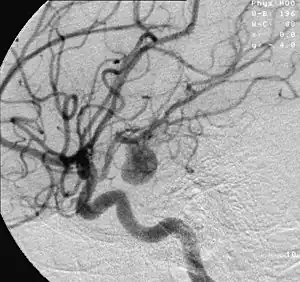

![]() | |

| Angiography of an aneurysm in a brain artery. The aneurysm is the large bulge in the center of the image. | |

Endovascular coiling was introduced by Italian neurosurgeon Guido Guglielmi at UCLA in 1989. It consists of passing a catheter into the femoral artery in the groin, through the aorta, into the brain arteries, and finally into the aneurysm itself. Platinum coils initiate a clotting reaction within the aneurysm that, if successful, fills the aneurysm dome and prevents its rupture.[41] A flow diverter can be used, but risks complications.[42]